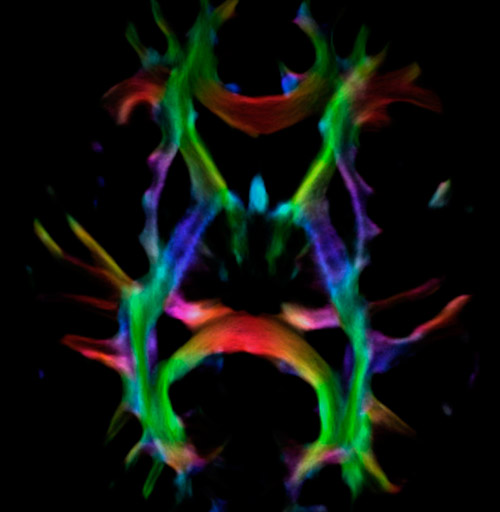

Fiber tracking from the left and right hippocampi to the fornix.

Fiber tracking from the left and right hippocampi to the fornix (green), and the corticospinal track based on a seed region of the posterior limb of the internal capsule.

Super-resolution directionally encoded color track-density imaging overlaid on T1-weighted structural MRI.